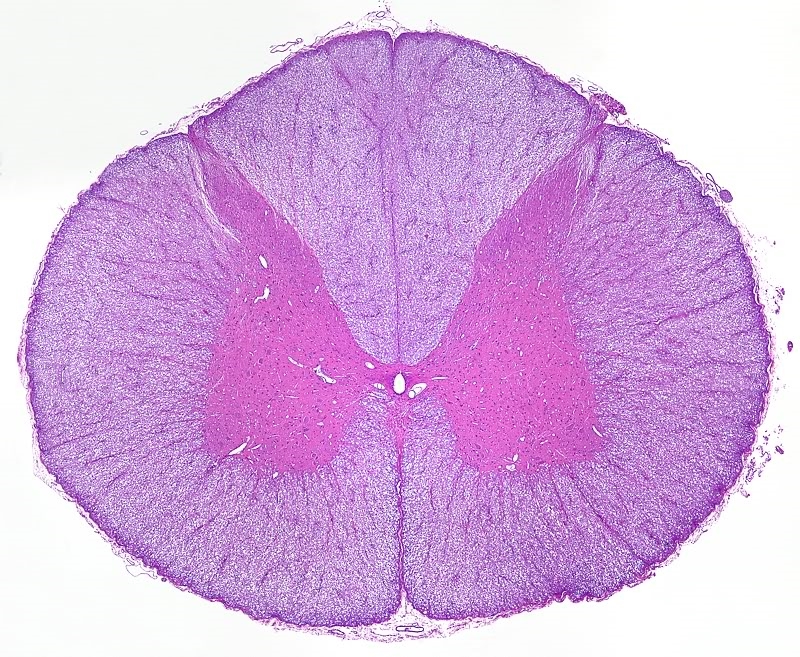

CaDi

Hmm...leider ist es wohl doch kein "Rezept" gegen diese fiesen Randbereiche. Die Niere hat mir schonmal

Probleme gemacht.

1x Plan

Ca. 30 Bilder

Unbearbeitet

Bearbeitet

Man sieht bei dem ersten Bild klar diese dunklen Ränder. Mit etwas Bearbeitung konnte ich die zum Teil entfernen, aber das Ergebnis hat mich schon etwas überrascht. Warum sollte das so von einem Präparat abhängig sein? Vielleicht weil es ein relativ homogenes Gewebe ist?

Hat jemand evtl. einen Tipp?

Mit der Bearbeitung versuche ich heute nochmal die Ränder ganz wegzubekommen. Vielleicht hat ja auch Autostitch seine Probleme mit den Bildern.